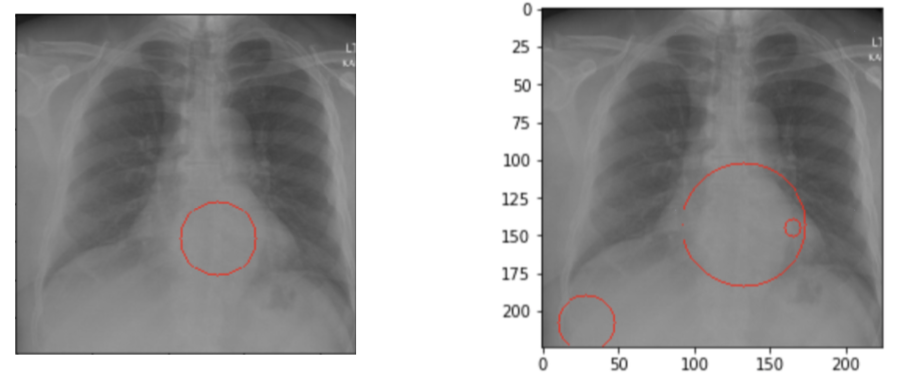

Above methodology is depicted in Figure 2. The ground truth for the patient is: ”There are degenerative changes in the spine. Borderline enlarged heart.”. The detection in the low sight sensitivity setting (bottom right) lets too much signal pass through. The result of this is detailed bounds around the spinal area and with an emphasis on the heart, accompanied with noise on the bottom left portion of the image. The higher sight sensitivity (bottom left) produces an averaged out explanation without the structured noise by trading off some true positive signals.